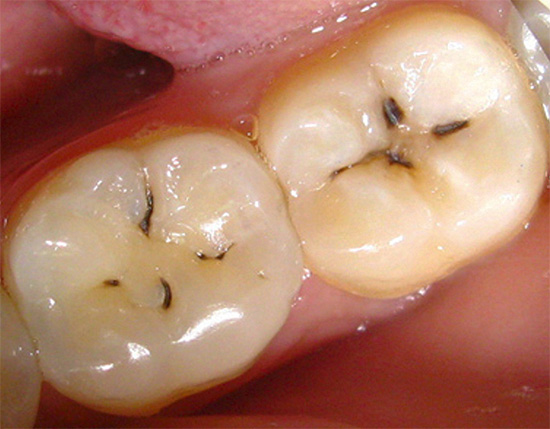

Sintomi e aspetto dei denti affetti da carie da fessure

La foto sotto mostra un esempio di carie da fessure. Nei punti più profondi delle fessure, sono chiaramente visibili le aree scure dello smalto, sotto le quali si trovano le principali aree di danno dentale: